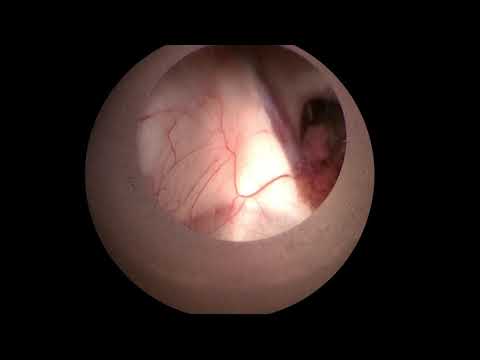

Hellow guys, Welcome to my website, and you are watching Cystocisternostomy of Sylvian Arachnoid Cyst with the LOTTA® Ventriculoscope. and this vIdeo is uploaded by Neurosurgery Greifswald at 2018-11-29T01:55:16-08:00. We are pramote this video only for entertainment and educational perpose only. So, I hop you like our website.